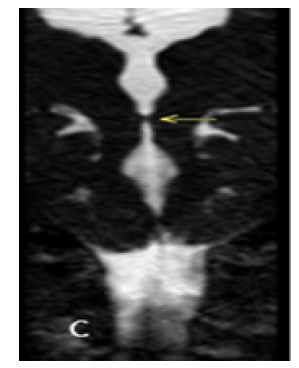

Figure 1C: Coronal reconstruction from Axial 1mm CT slices. Dilated lateral and third ventricles with normal appearing fourth ventricle. Yellow arrow points to the AW/D.

MRI brain was performed in a 3T Siemens Vireo magnet. The additional axial CISS 3D sequence was obtained with isotropic 0.6 x 0.6 x 0.6 voxels taking 7.18 minutes. Sagittal and Coronal reconstructions clearly demonstrated the AW/D Despite the Motion ArtiFact (Figure 2B) (Figure 2C).